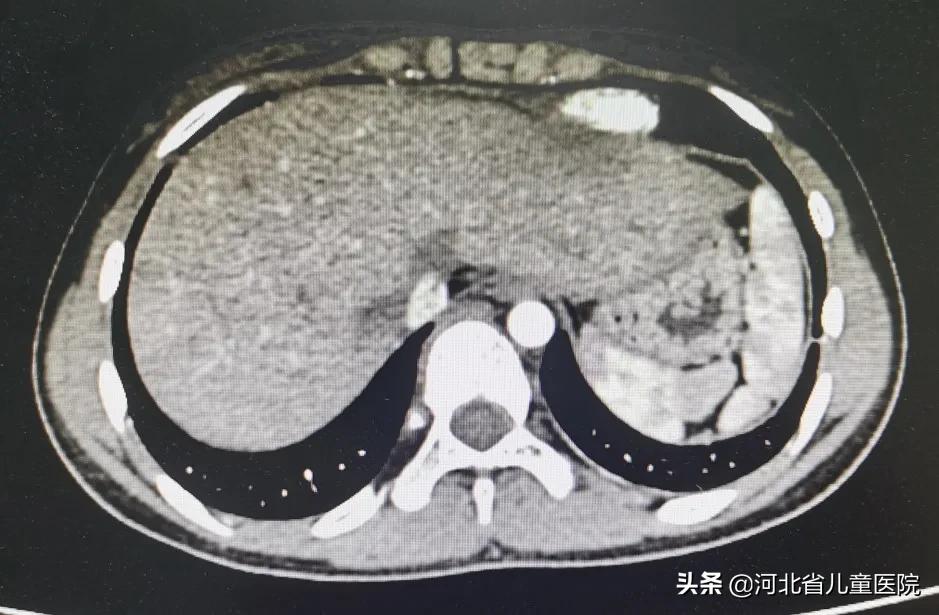

今年年初,10岁的多多(化名)出现间断性腹痛、腹胀2周后来院就诊,腹部超声提示腹腔内有大量积液。入院后进行心脏超声、肝胆超声、胸腹部CT等检查,结合病史诊断为布-加综合征(肝静脉阻塞型)。多多肝静脉开口处堵塞,大量血液瘀滞在肝脏,肝脏持续性肿大,肠道水肿,大量腹水,肝功能持续恶化,病情日渐加重。

术后六个月的时间里,患儿共复查14次凝血四项,4次肝脏超声,2次腹部强化CT,主治医师高杨始终同多多家长保持联系,调整抗凝策略,抗凝药用药量增多会造成出血风险,用量少则有可能导致人工通路再闭塞。日前,多多的复查结果令人满意,恢复良好。

进行介入手术后半年